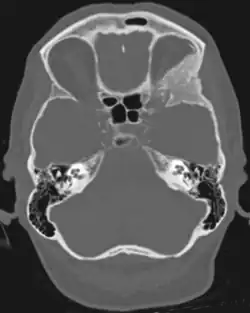

Sphenoid wing meningioma

A sphenoid wing meningioma is a benign brain tumor near the sphenoid bone.

Sphenoid wing meningiomas are diagnosed by the combination of suggestive symptoms from the history and physical and neuroimaging by magnetic resonance imaging (MRI) or computer averaged tomography (CT). Tumors growing in the inner wing (clinoidal) most often cause direct damage to the optic nerve leading especially to a decrease in visual acuity, progressive loss of color vision, defects in the field of vision (especially cecocentral), and an afferent pupillary defect. If the tumor continues to grow and push on the optic nerve, all vision will be lost in that eye as the nerve atrophies. Proptosis, or anterior displacement of the eye, and palpebral swelling may also occur when the tumor impinges on the cavernous sinus by blocking venous return and leading to congestion. Damage to cranial nerves in the cavernous sinus leads to diplopia. Cranial nerve VI is often the first affected, leading to diplopia with lateral gaze. If cranial nerve V-1 is damaged, the patient will have pain and altered sensation over the front and top of the head. Horner's syndrome may occur if nearby sympathetic fibers are involved.

Tumors found in the external third of the sphenoid are of two types: en-plaque and globoid meningiomas. En plaque meningiomas characteristically lead to slowly increasing proptosis with the eye angled downward. Much of this is due to reactive orbital hyperostosis. With invasion of the tumor into the orbit, diplopia is common. Patients with globoid meningiomas often present only with signs of increased intracranial pressure. This leads to various other symptoms including headache and a swollen optic disc. The differential diagnosis for sphenoid wing meningioma includes other types of tumors such as optic nerve sheath meningioma, cranial osteosarcoma, metastases, and also sarcoidosis. Following the physical exam, the diagnosis is confirmed with neuro-imaging. Either a head CT or MRI with contrast such as gadolinium is useful, as meningiomas often show homogenous enhancement. Angiography looking for signs like stretched arteries may be used to supplement evaluation of vascular involvement and to determine whether embolization would be helpful if surgery is being considered.